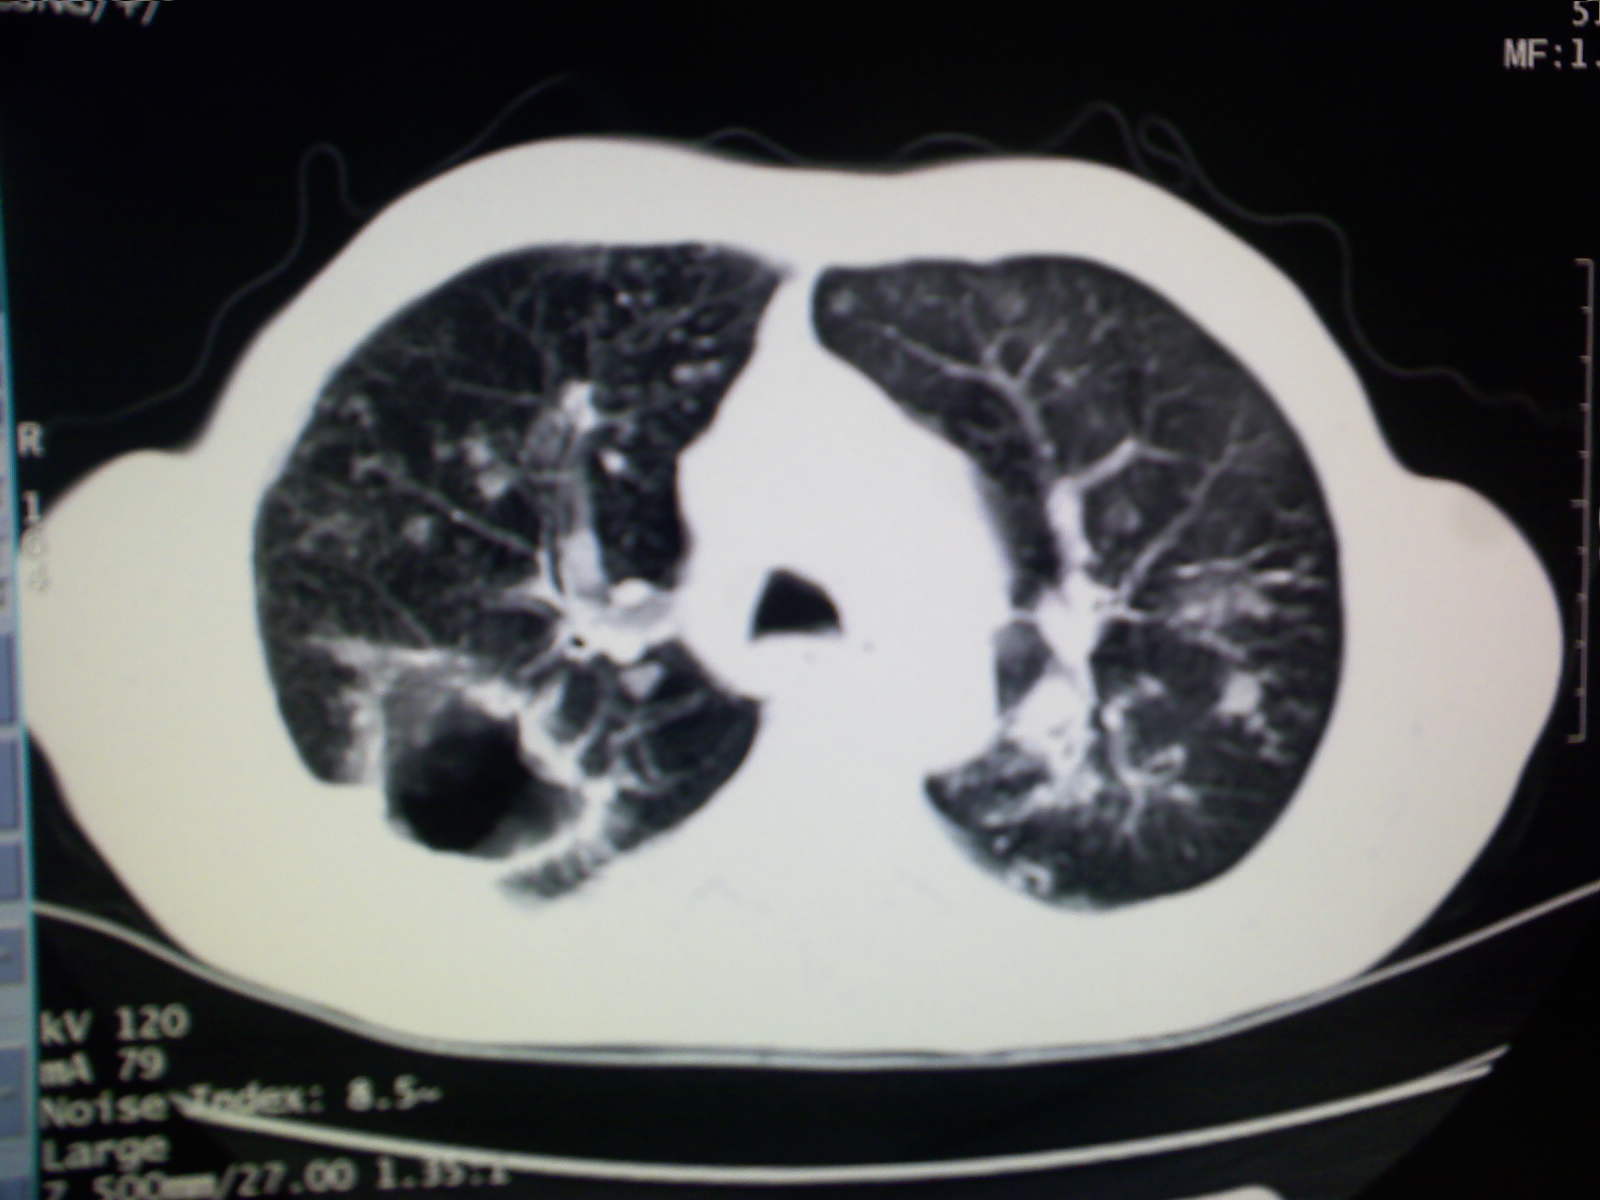

以下是引用卜一在2009-4-11 15:50:00的发言:[br]双肺继发性肺结核伴空洞形成,不排除合并霉菌感染!(病灶呈多形态 多特征 散在分布)。另:合并支气管扩张征伴感染!

以下是引用主力军在2009-4-11 15:55:00的发言:[br]两肺继发性肺结核可能性大。

以下是引用康鹏在2009-4-11 16:30:00的发言:[br]双肺继发性肺结核伴空洞形成合并感染[br]支气管扩张合并感染